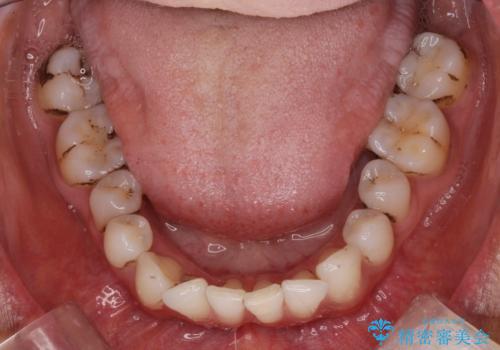

着色が気になる(エアフロー)

- 着色が気になるとの事で来院。

エアフローでしっかり着色を取り除きました。

着色が目立たなくなり大変満足して頂けました。